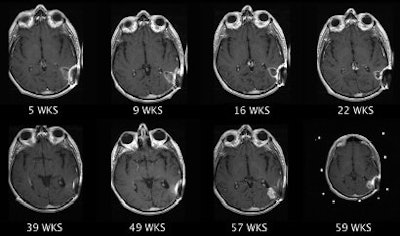

| Clinical MRI images of a patient after At-211 ch81C6 therapy. After At-211 ch81C6 administration, surgically created resection cavity rim enhancement gradually became more prominent, as surgically created resection cavity retracted. Focal nodular enhancement noted 57 weeks after At-211 ch81C6 administration was confirmed to the recurrent anaplastic oligodendroglioma. Image courtesy of Duke University Medical Center and reprinted with permission from "Clinical Experience with α-Particle-Emitting 211At: Treatment of Recurrent Brain Tumor Patients with 211At-Labeled Chimeric Antitenascin Monoclonal Antibody 81C6," Michael R. Zalutsky, David A. Reardon, Gamal Akabani, R. Edward Coleman, Allan H. Friedman, Henry S. Friedman, Roger E. McLendon, Terence Z. Wong, and Darell D. Bigner. January 2008 Journal of Nuclear Medicine. |

The therapy also extended patients' survival rates by one to three years, with a median time of 54.1 weeks. Without treatment, patients have a life expectancy of approximately six months.